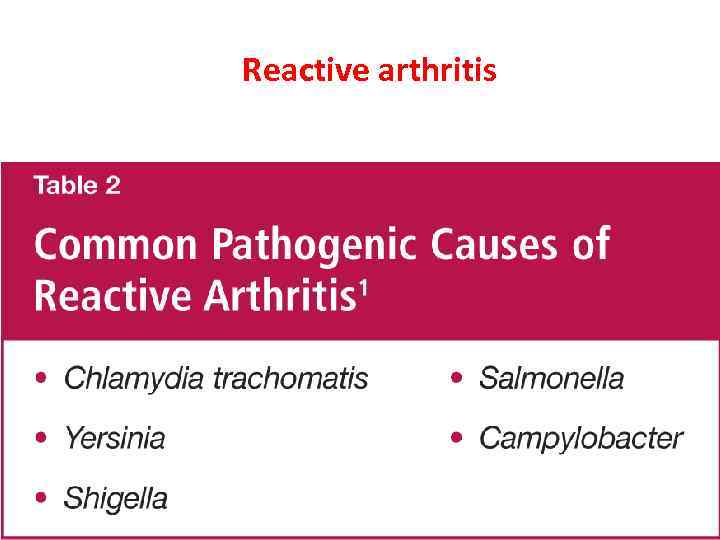

Reactive arthritis